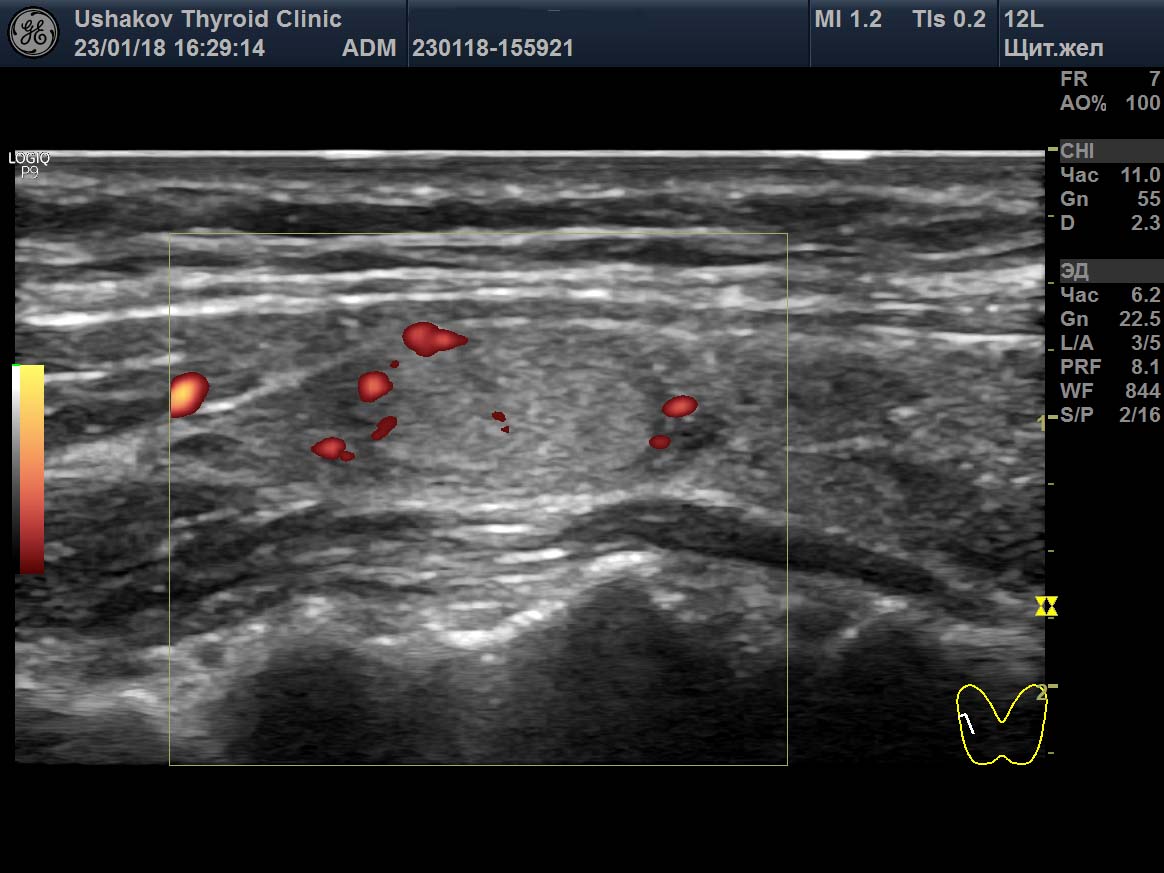

Гипертиреоз узи

Гипертиреоз узи 110 фото